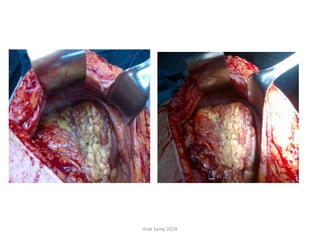

Case Presentation

• 65 years od female patient presenting with

large left iliac mass extending to left lumbar

and hypochondrial regions.

• History 2 months ago of excision of a small

exuberant heel ulcer about 1.5 X 1 cm.

• Pathology revealed: Amelanotic melanoma,

T4b, Clark’s level V; focally infiltrated surgical

margins.

• Exploration done on 15-01-2012 through a

generous midline incision revealed a large

cystic mass covered by omentum occupying

the lt. iliac, lumbar and hypochondrial fossae.

• The mass was dissected from lt. ureter and

iliac vessels inferiorly up to lt. kidney, stomach

and spleen superiorly